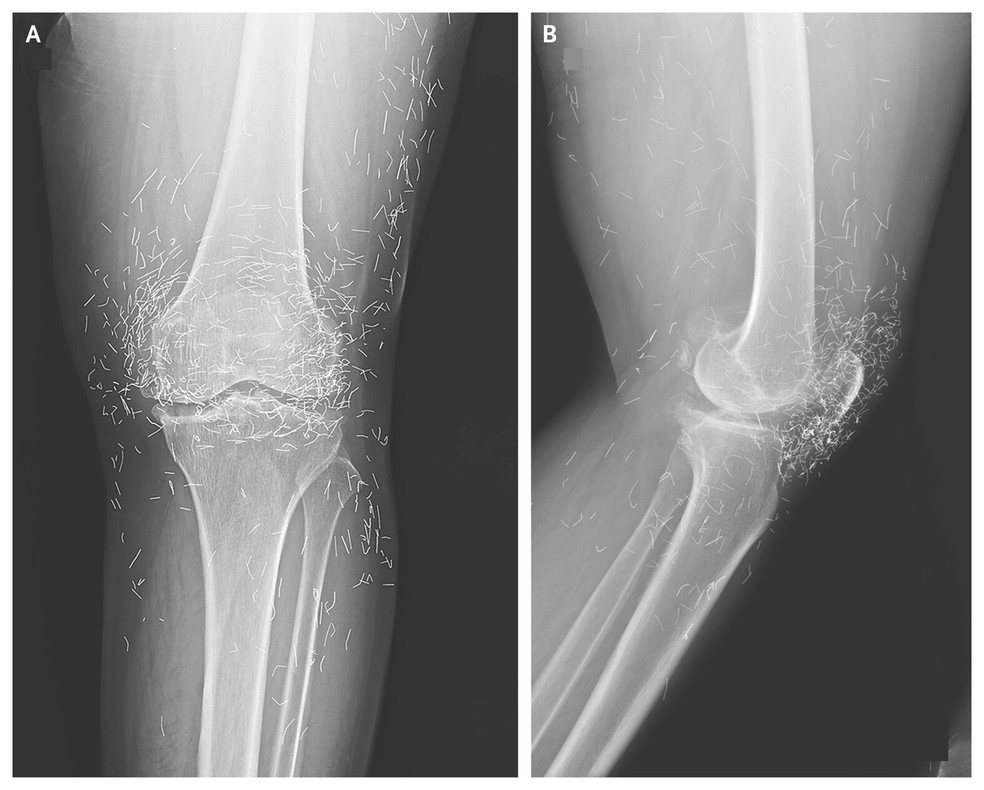

Uma mulher de 65 anos buscou atendimento relatando dores fortes nos joelhos depois de um diagnóstico de osteoartrite. O médico pediu um raio-X para avaliar a região e levou um susto com a imagem: havia vários pontos brilhantes no tecido ao redor da articulação. Segundo o especialista, eram “fios de ouro” deixados por um tratamento alternativo ao qual ela havia recorrido (veja a imagem acima).

Como isso é feito? Durante a terapia, pequenas partículas — ditas de ouro — são colocadas na ponta da agulha e acabam sendo inseridas no corpo. Há dezenas de posts em redes sociais oferecendo esse tipo de serviço como “tratamento para dor”.

Essas partículas não conseguem ser absorvidas pelo corpo e acabaram ficando acumuladas na região já doente e ampliando a dor.